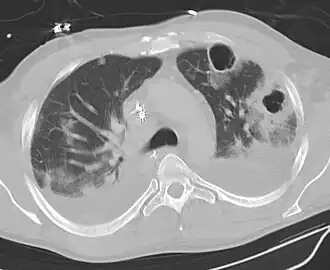

Abscesso pulmonar (português brasileiro) ou abcesso pulmonar (português europeu) é a necrose do tecido pulmonar e a formação de cavidades (com mais de 2 cm) contendo resíduos necróticos ou fluido, causado por infecções microbianas.

Estas cavidades preenchidas de pus são comumente causadas por aspiração, que pode ocorrer durante estadios de consciência alterados. O alcoolismo é a condição mais comum que predispõe para abcessos pulmonares, pós pneumonia aspirativa.